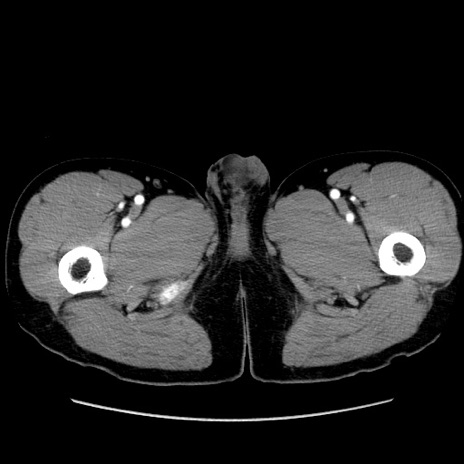

症例36(横断像)

【症例】20歳代 男性

【主訴】心窩部痛

【現病歴】今朝より上腹部痛あり。一旦軽快していたが再度出現したため救急要請。昨日夕に白身の魚を含む刺身を食べた。

【身体所見】BP 136/89mmHg、HR 74/min、BT 37.0℃、腹部:膨満、軟、心窩部に圧痛あり。反跳痛なし、筋性防御なし、腸雑音やや亢進あり。

【データ】WBC 17700、CRP 0.48